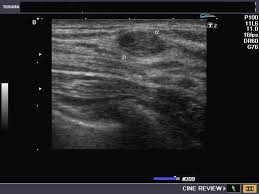

полость с густым содержимым.